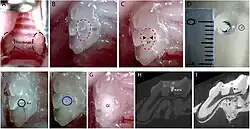

- On voit à la fois des dents temporaires et des dents définitives.

- Radiographie de dents saines (prémolaires, molaires, dent de sagesse incluse) et cariées (2e prémolaire supérieure et 1re molaire supérieure).